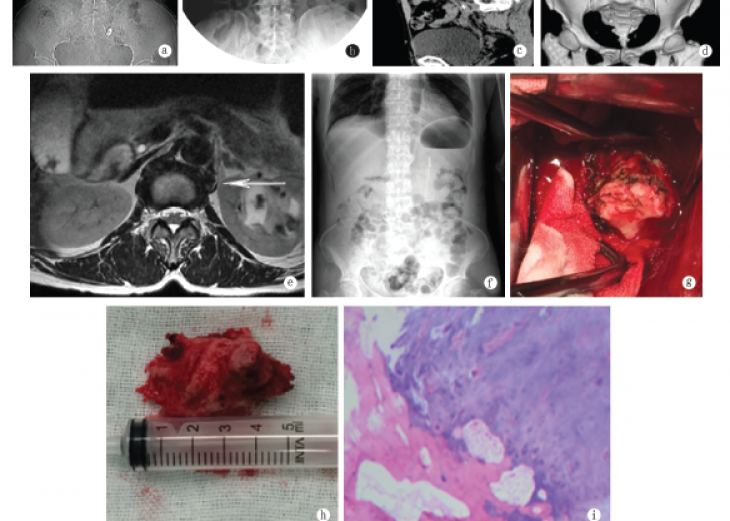

骨软骨瘤是一种发生在骨表面,顶端有软骨帽覆盖的良性骨肿瘤。大多发生在长管状骨的干骺端,约占骨肿瘤的9.3%,占骨良性肿瘤的36%左右。然而,发生在脊柱的骨软骨瘤在临床上较为罕见。除此之外,...